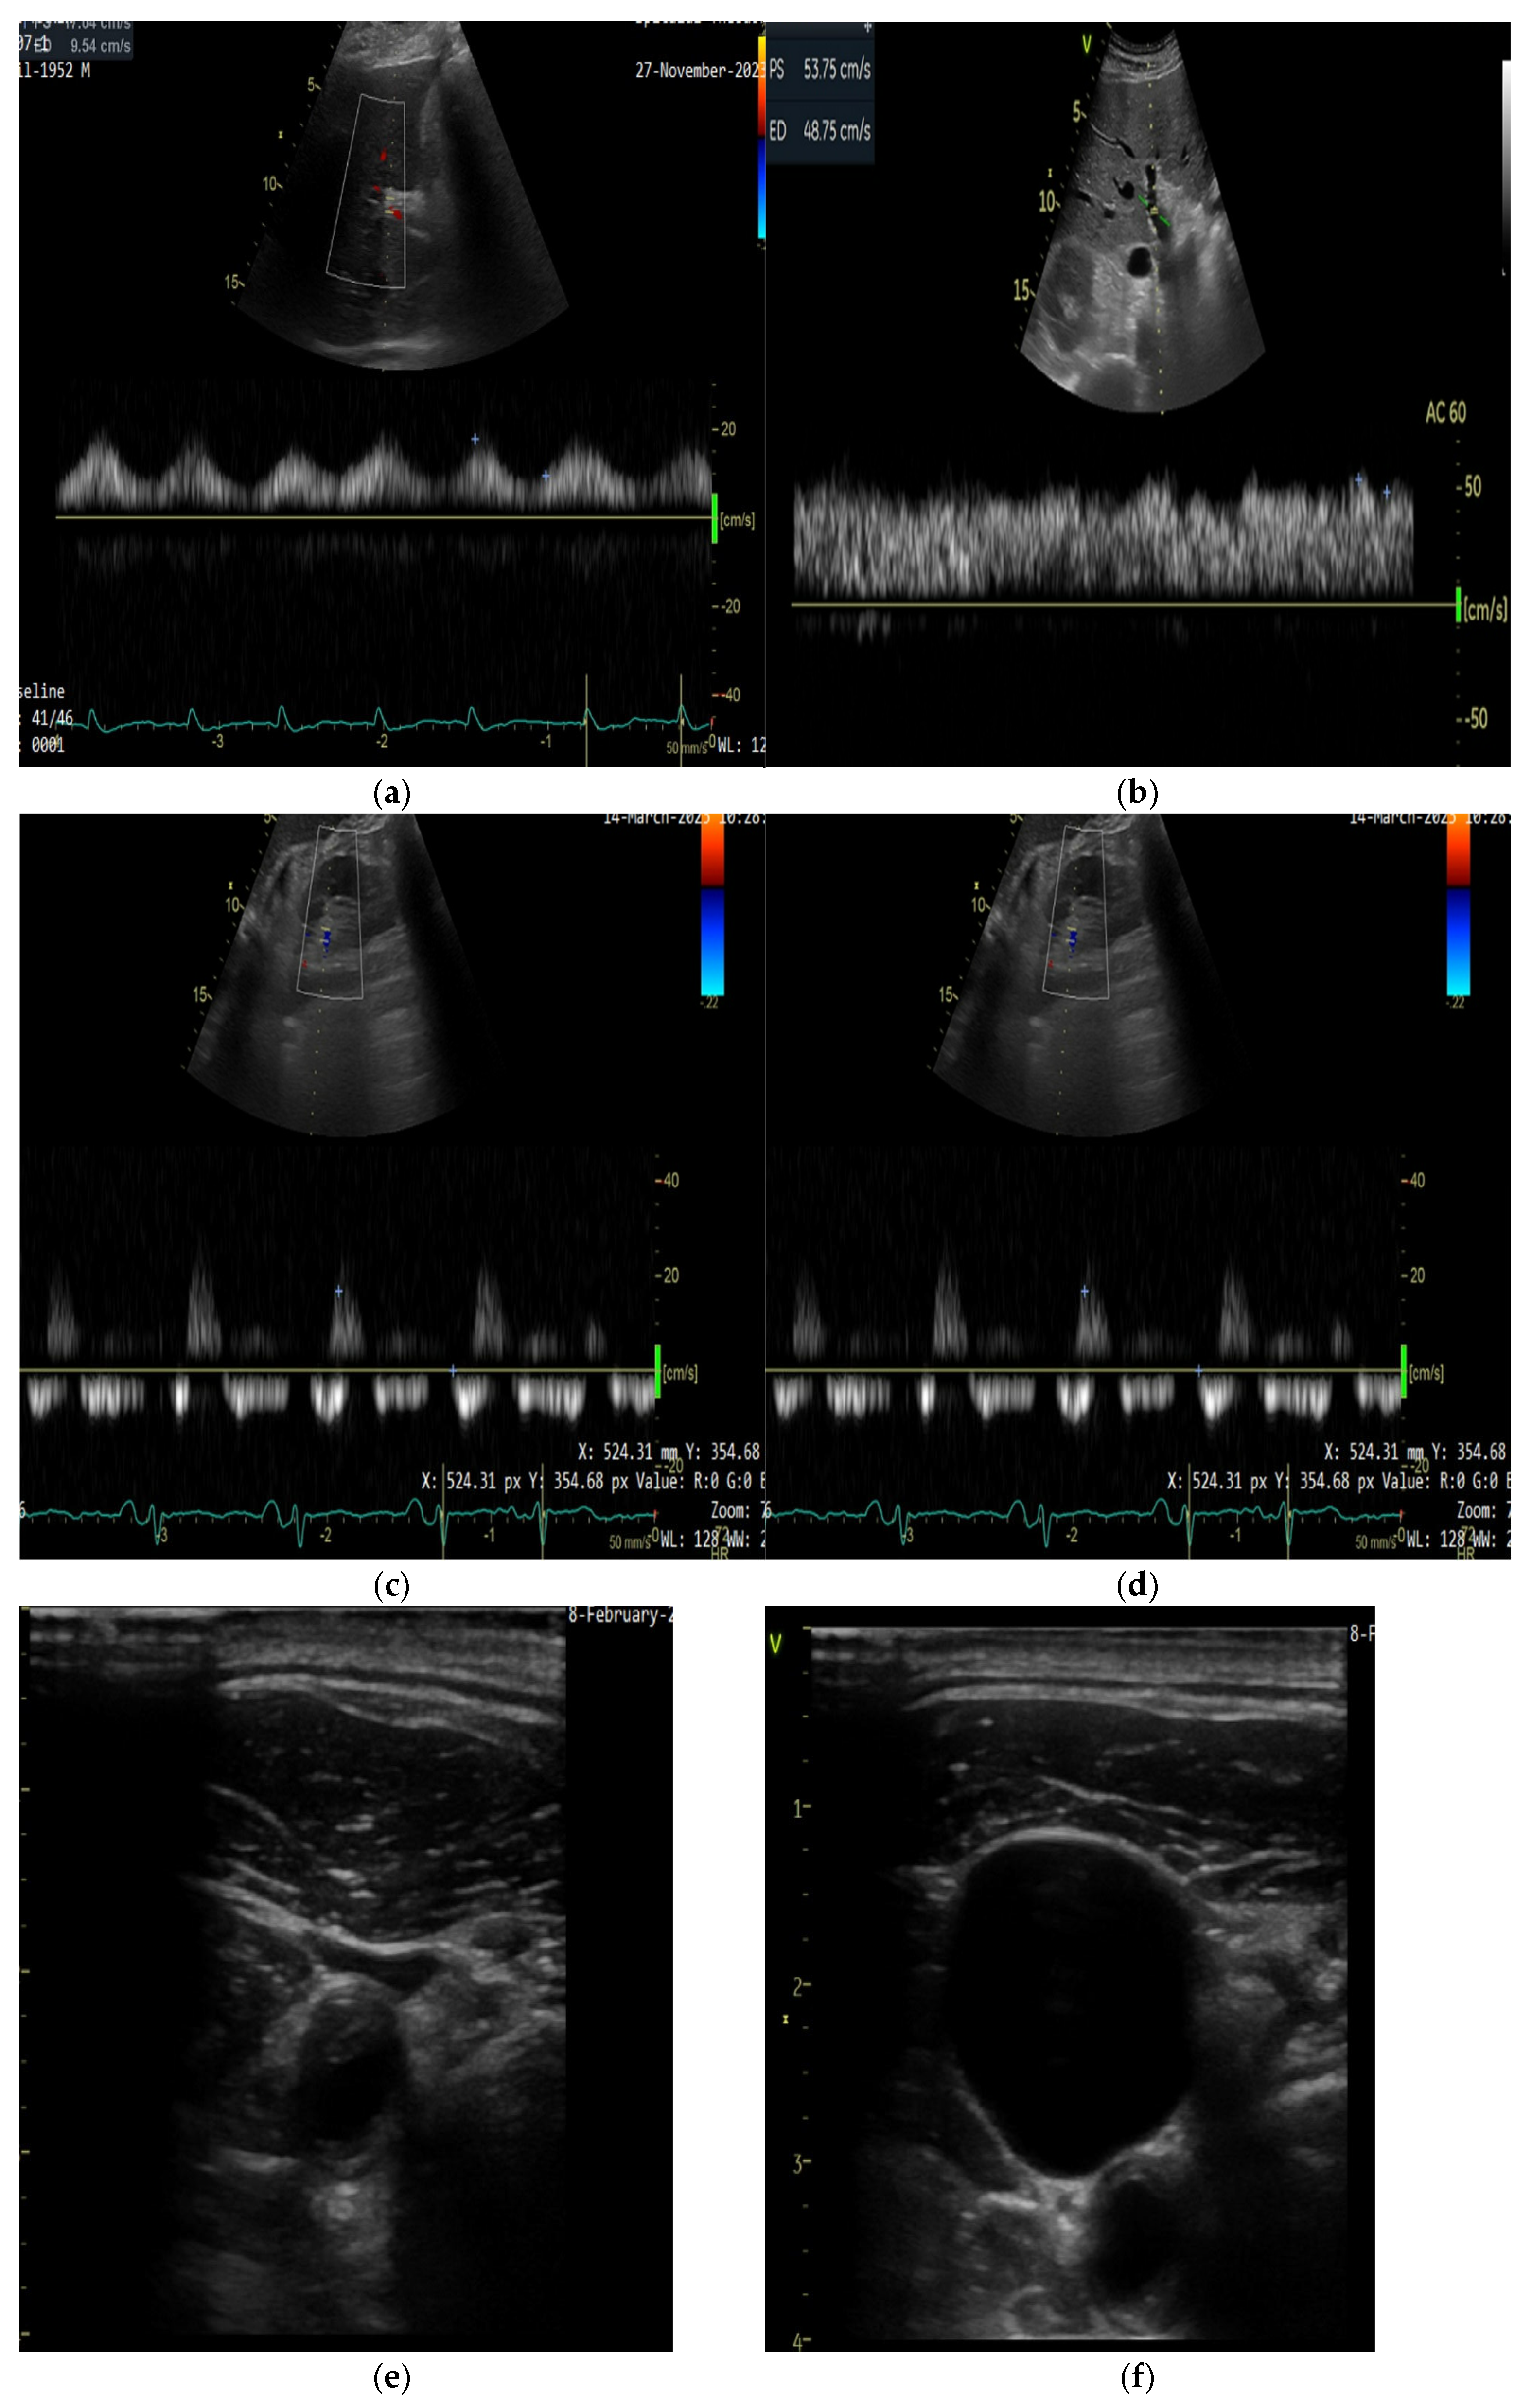

5.2.1. Ultrasound Assessment of Systemic Venous Congestion: Role of VExUS

5.2.2. Technical Aspects of Doppler Evaluation

- Grigore, M.; Grigore, A.-M.; Ilieșiu, A.-M. Portal Vein Pulsatility: A Valuable Approach for Monitoring Venous Congestion and Prognostic Evaluation in Acute Decompensated Heart Failure. Diagnostics 2024, 14, 2029. [Google Scholar] [CrossRef] [PubMed]